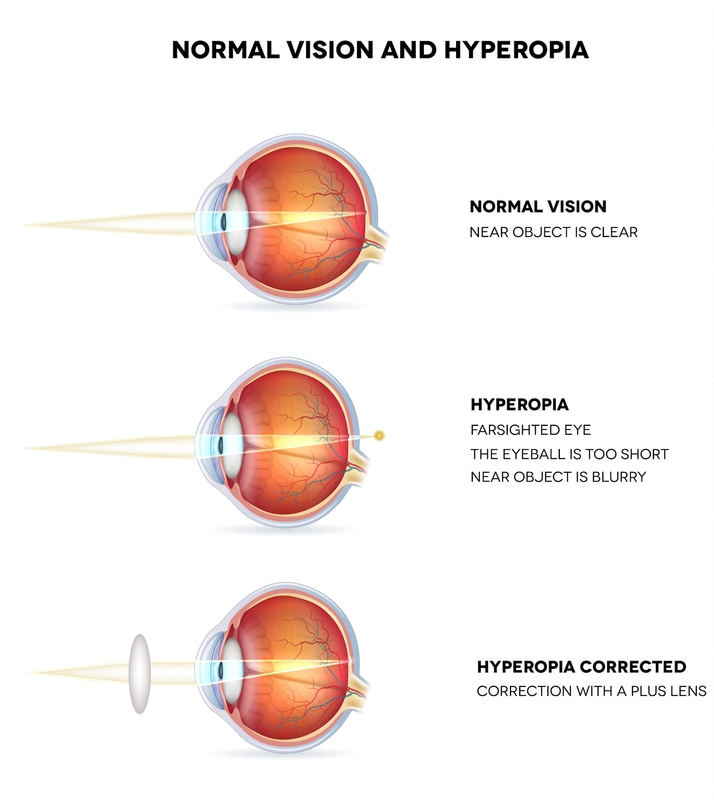

Do you offer laser vision correction?Yes, we provide consultations for LASIK and other laser vision correction procedures. Our experts work closely with trusted surgeons to ensure safe and precise outcomes.What options are available for treating dry eyes?We offer customized treatments, including lubricating drops, prescription medicines, and advanced solutions such as punctal plugs or light therapy for long-term relief.Can I get my glasses on the same day?In most cases, yes. Our in-house optical center can prepare your prescription glasses on the same day or within 24 hours, depending on lens type and availability.Do you provide treatment for glaucoma and cataracts?Yes, we specialize in diagnosing and managing glaucoma, cataracts, and other eye diseases. Our team ensures timely treatment plans and advanced surgical options when needed.Are contact lenses suitable for children and teenagers?Absolutely. With proper guidance and care, contact lenses can be safely worn by children aged 10 and above. Our specialists help select lenses best suited for young eyes.